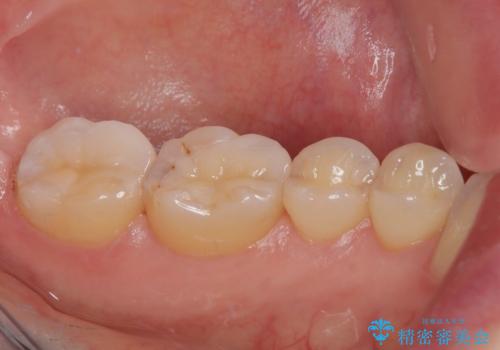

- 銀歯がとれたのでやり替えたいとのことで来院された患者様です。来院時特に症状もなく金属の詰め物(メタルインレー)がとれたのでセラミックの詰め物(セラミックインレー)にやり替えていくことになりました。また患者様のご希望によりひとつ後ろの歯の金属の詰め物(メタルインレー)のやり替えも同時に治療していくことになりました。

拡大鏡視野下で、金属の詰め物(メタルインレー)、保険のプラスチック、虫歯の除去を行い、セラミックインレーに適した形に整えました。